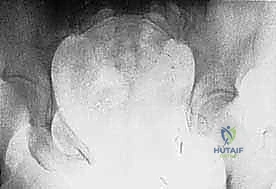

- Plain Radiography (FIG 2): While of limited value for early lesions, it provides an initial overview. As you can see in Figure 2A, we have a large lytic lesion of the right periacetabular region. Figure 2C shows a cartilage-forming lesion in the left ilium. However, plain films often underestimate the true extent of these tumors.

* CT with Intravenous Contrast and 3D Reconstruction (FIG 3): This is our workhorse for assessing bone involvement, destruction, and the critical relationship between the tumor and major pelvic blood vessels. It reveals any distortion of the pelvic anatomy and guides resectability. Figure 3A clearly shows extensive bone destruction and tumor extension into the pelvis and gluteal region. Figure 3C highlights an extensive tumor on the medial aspect of the ilium with destruction of the inner table.